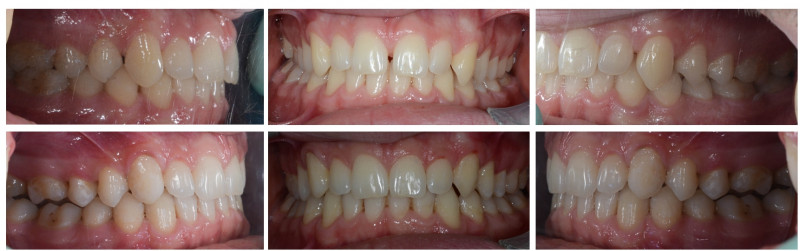

Slučaj 1: ispravljanje otvorenog zagriza i kompresije Invisalign full terapijom

Slučaj 2: ispravljanje kompresije Invisalign full terapijom- u ovom slučaju je izvađen jedan donji sjekutić

Slučaj 3: ispravljanje kompresije Invisalign full terapijom

Slučaj 4: ispravljanje kompresije Invisalign full terapijom

Slučaj 5: ispravljanje kompresije i križnog zagriza Invisalign full terapijom

Slučaj 6: ispravljanje kompresije i dubokog zagriza Invisalign full terapijom